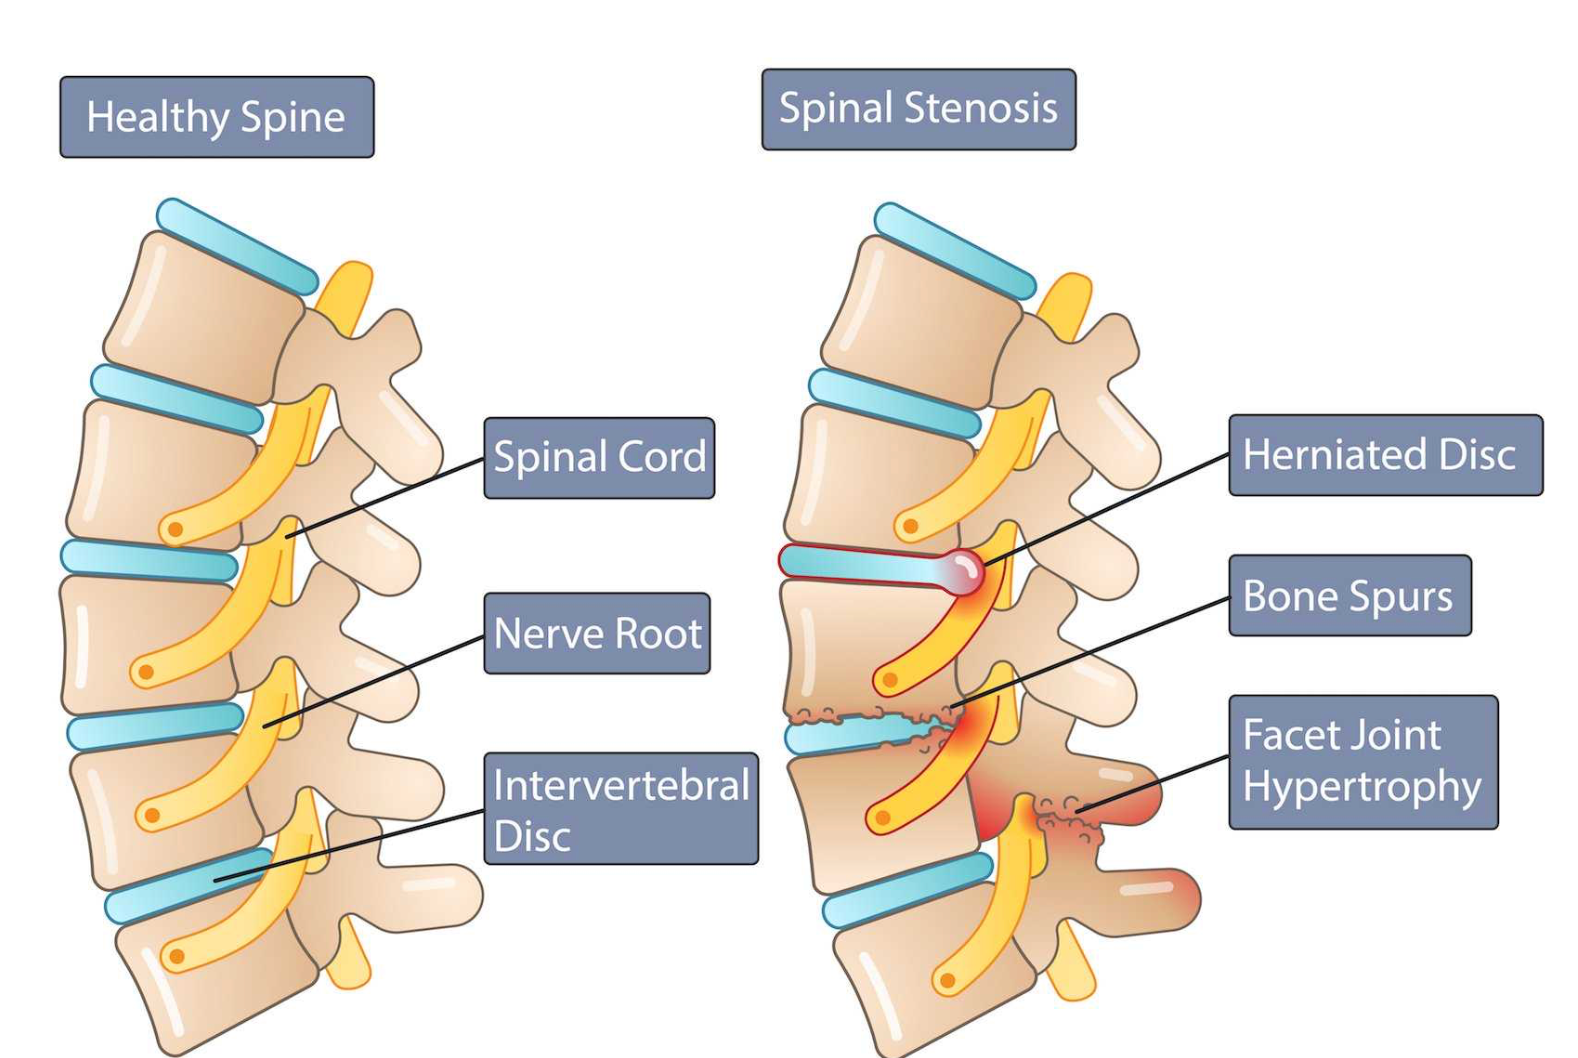

Lumbar canal stenosis is a condition in which the spinal canal in the lower back becomes narrowed, leading to compression of the spinal nerves. It most commonly develops due to age-related degenerative changes in the spine and is a frequent cause of back pain, leg pain, and difficulty walking in middle-aged and elderly individuals.

Lumbar canal narrowing usually occurs gradually and may result from one or more of the following:

- Degenerative disc bulge or disc height loss

- Thickening of spinal ligaments (ligamentum flavum hypertrophy)

- Facet joint arthritis and bone spur formation